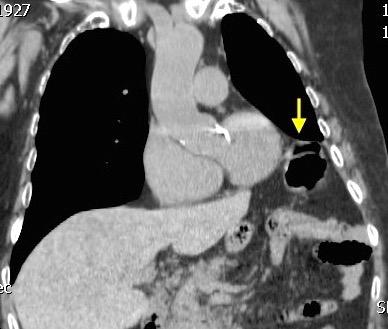

Parálisis frénica transitoria tras cirugía de válvula aórtica

Parálisis frénica transitoria post cirugía cardiaca (10%).

Puede acompañarse de atelectasia del LII.

Benjamin JJ et al. . Left lower lobe atelectasis and consolidation following cardiac surgery: the effect of topical cooling on the phrenic nerve. Radiology 1982